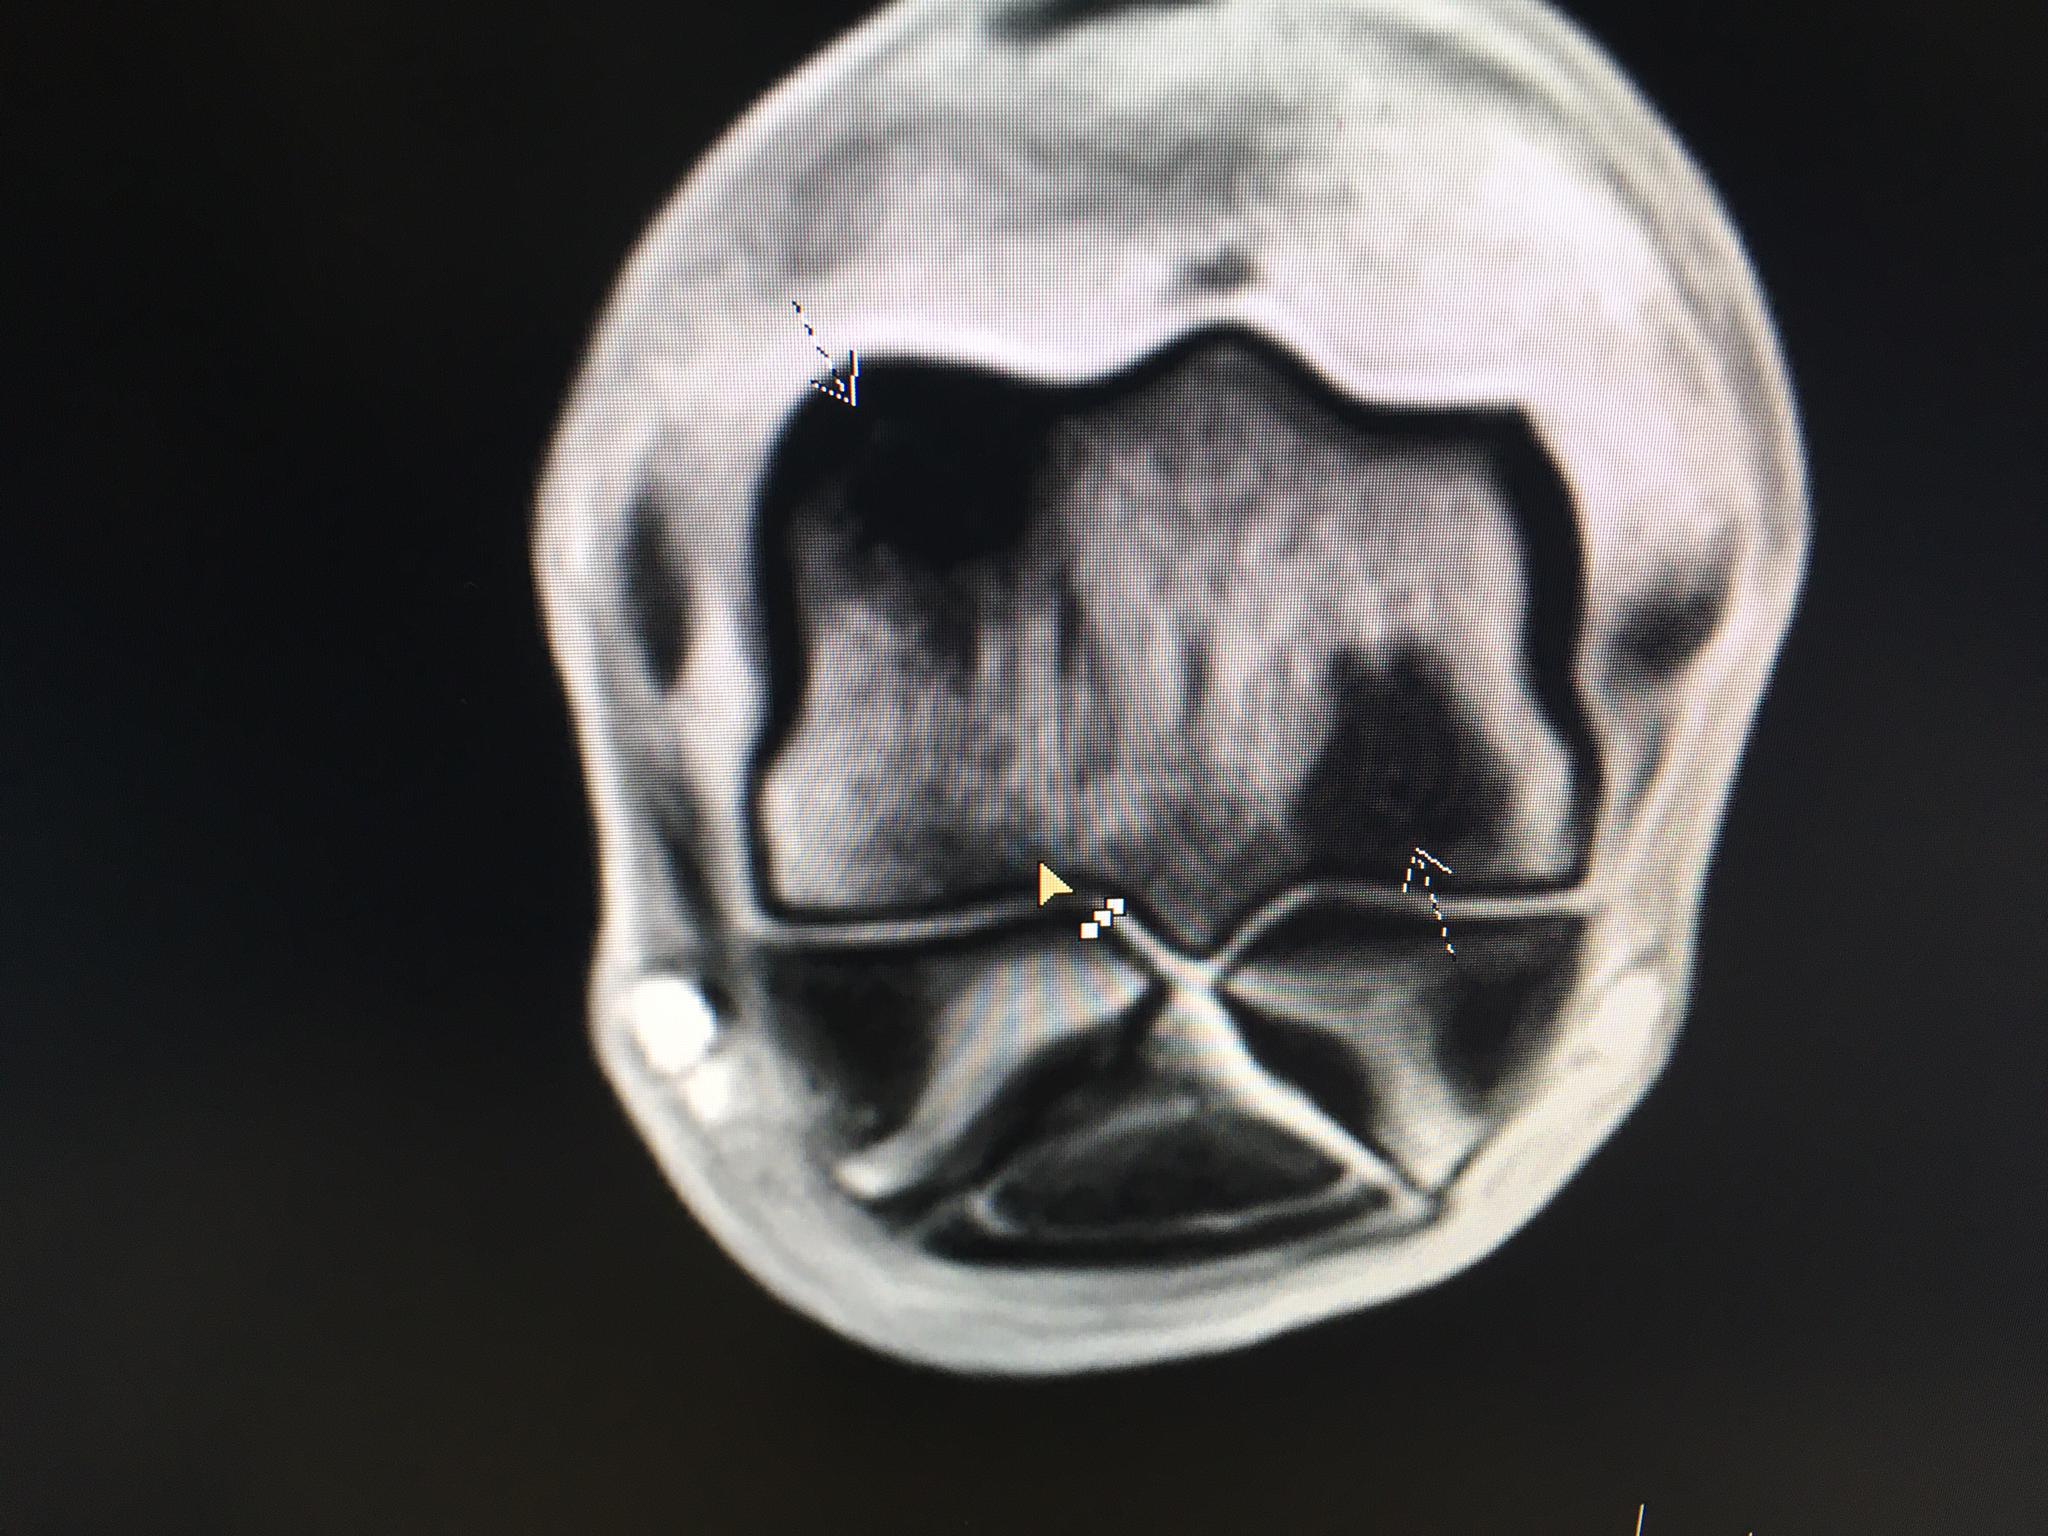

Heute gilt die ganze Aufmerksamkeit VESSILLO. Bei ihm wurden leider am letzten Dienstag Verletzungen festgestellt, die einen operativen Eingriff notwendig machten. Auf den Röntgenbildern war rein gar nichts zu sehen. Doch eine eingehende MRI-Untersuchung brachte es an den Tag: Zwei Fissuren und ein Mini-Ödem (ein Kleinst-Bluterguss im Knochen) ganz unten im Röhrbein, beim Fesselgelenk. Zum Glück hatten wir insistiert und diese Untersuchung gemacht. Sonst hätte es ganz böse enden können.

Das eine MRI-Bild...

...und von anderer Seite.